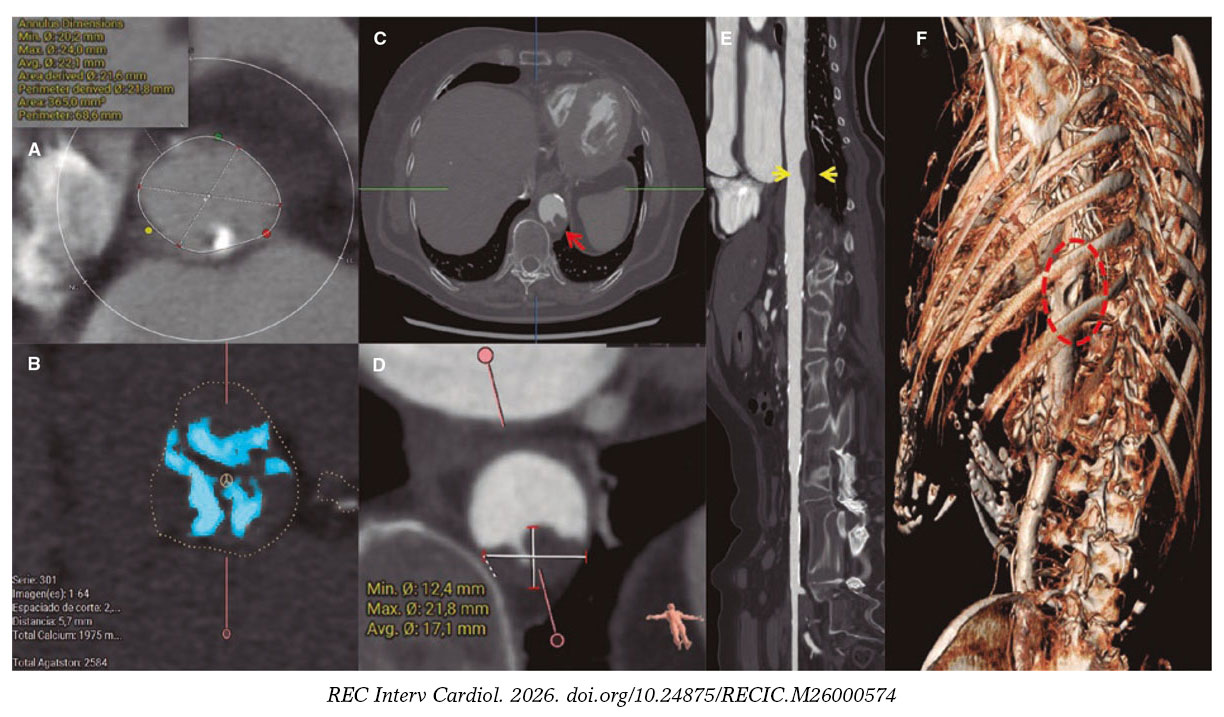

Mujer de 86 años con estenosis aórtica grave sintomática. Previo al implante percutáneo de válvula aórtica (TAVI) se realizó una tomografía computarizada cardiaca y aórtica que mostró un perímetro del anillo aórtico de 68 mm (figura 1A) y una calcificación valvular de 2.584 unidades Agatston (figura 1B), en la aorta torácica descendente una placa blanda con superficie irregular (figura 1C,E, flechas; figura 1F, elipse) de 22 × 12 mm (figura 1D), y unos adecuados accesos femorales.

Figura 1.